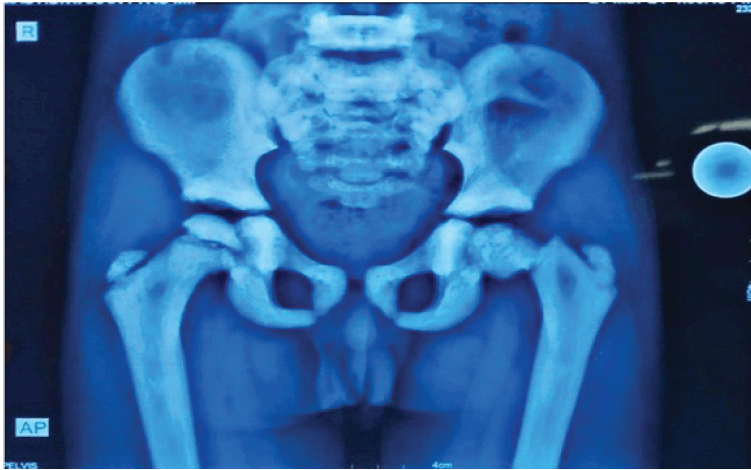

A 6-year-old boy presented to the emergency department with pain and inability to bear weight on the left lower limb following a trivial slip and fall. Clinical examination revealed restricted and painful movements of the left hip. Radiographs of the pelvis demonstrated a fracture of the left femoral neck with marked sclerosis of the pelvic bones and proximal femur, raising suspicion of a pathological fracture (Fig. 1).

Figure 1: Anteroposterior radiograph of pelvis with both hips at presentation showing left femoral neck fracture with diffuse bony sclerosis.